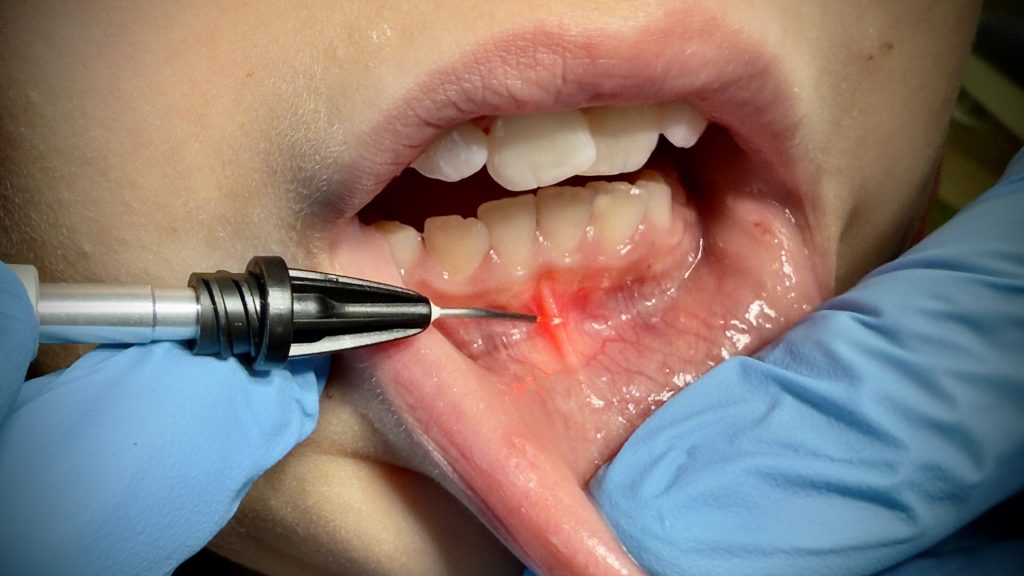

Die Behandlung mit energiereichen Lichtbündeln, auch als Lasertherapie bekannt, stellt in zahlreichen medizinischen Disziplinen einen bedeutenden technischen Fortschritt dar. Sie hat sich als äußerst effektiv und vielseitig erwiesen, … weiterlesen